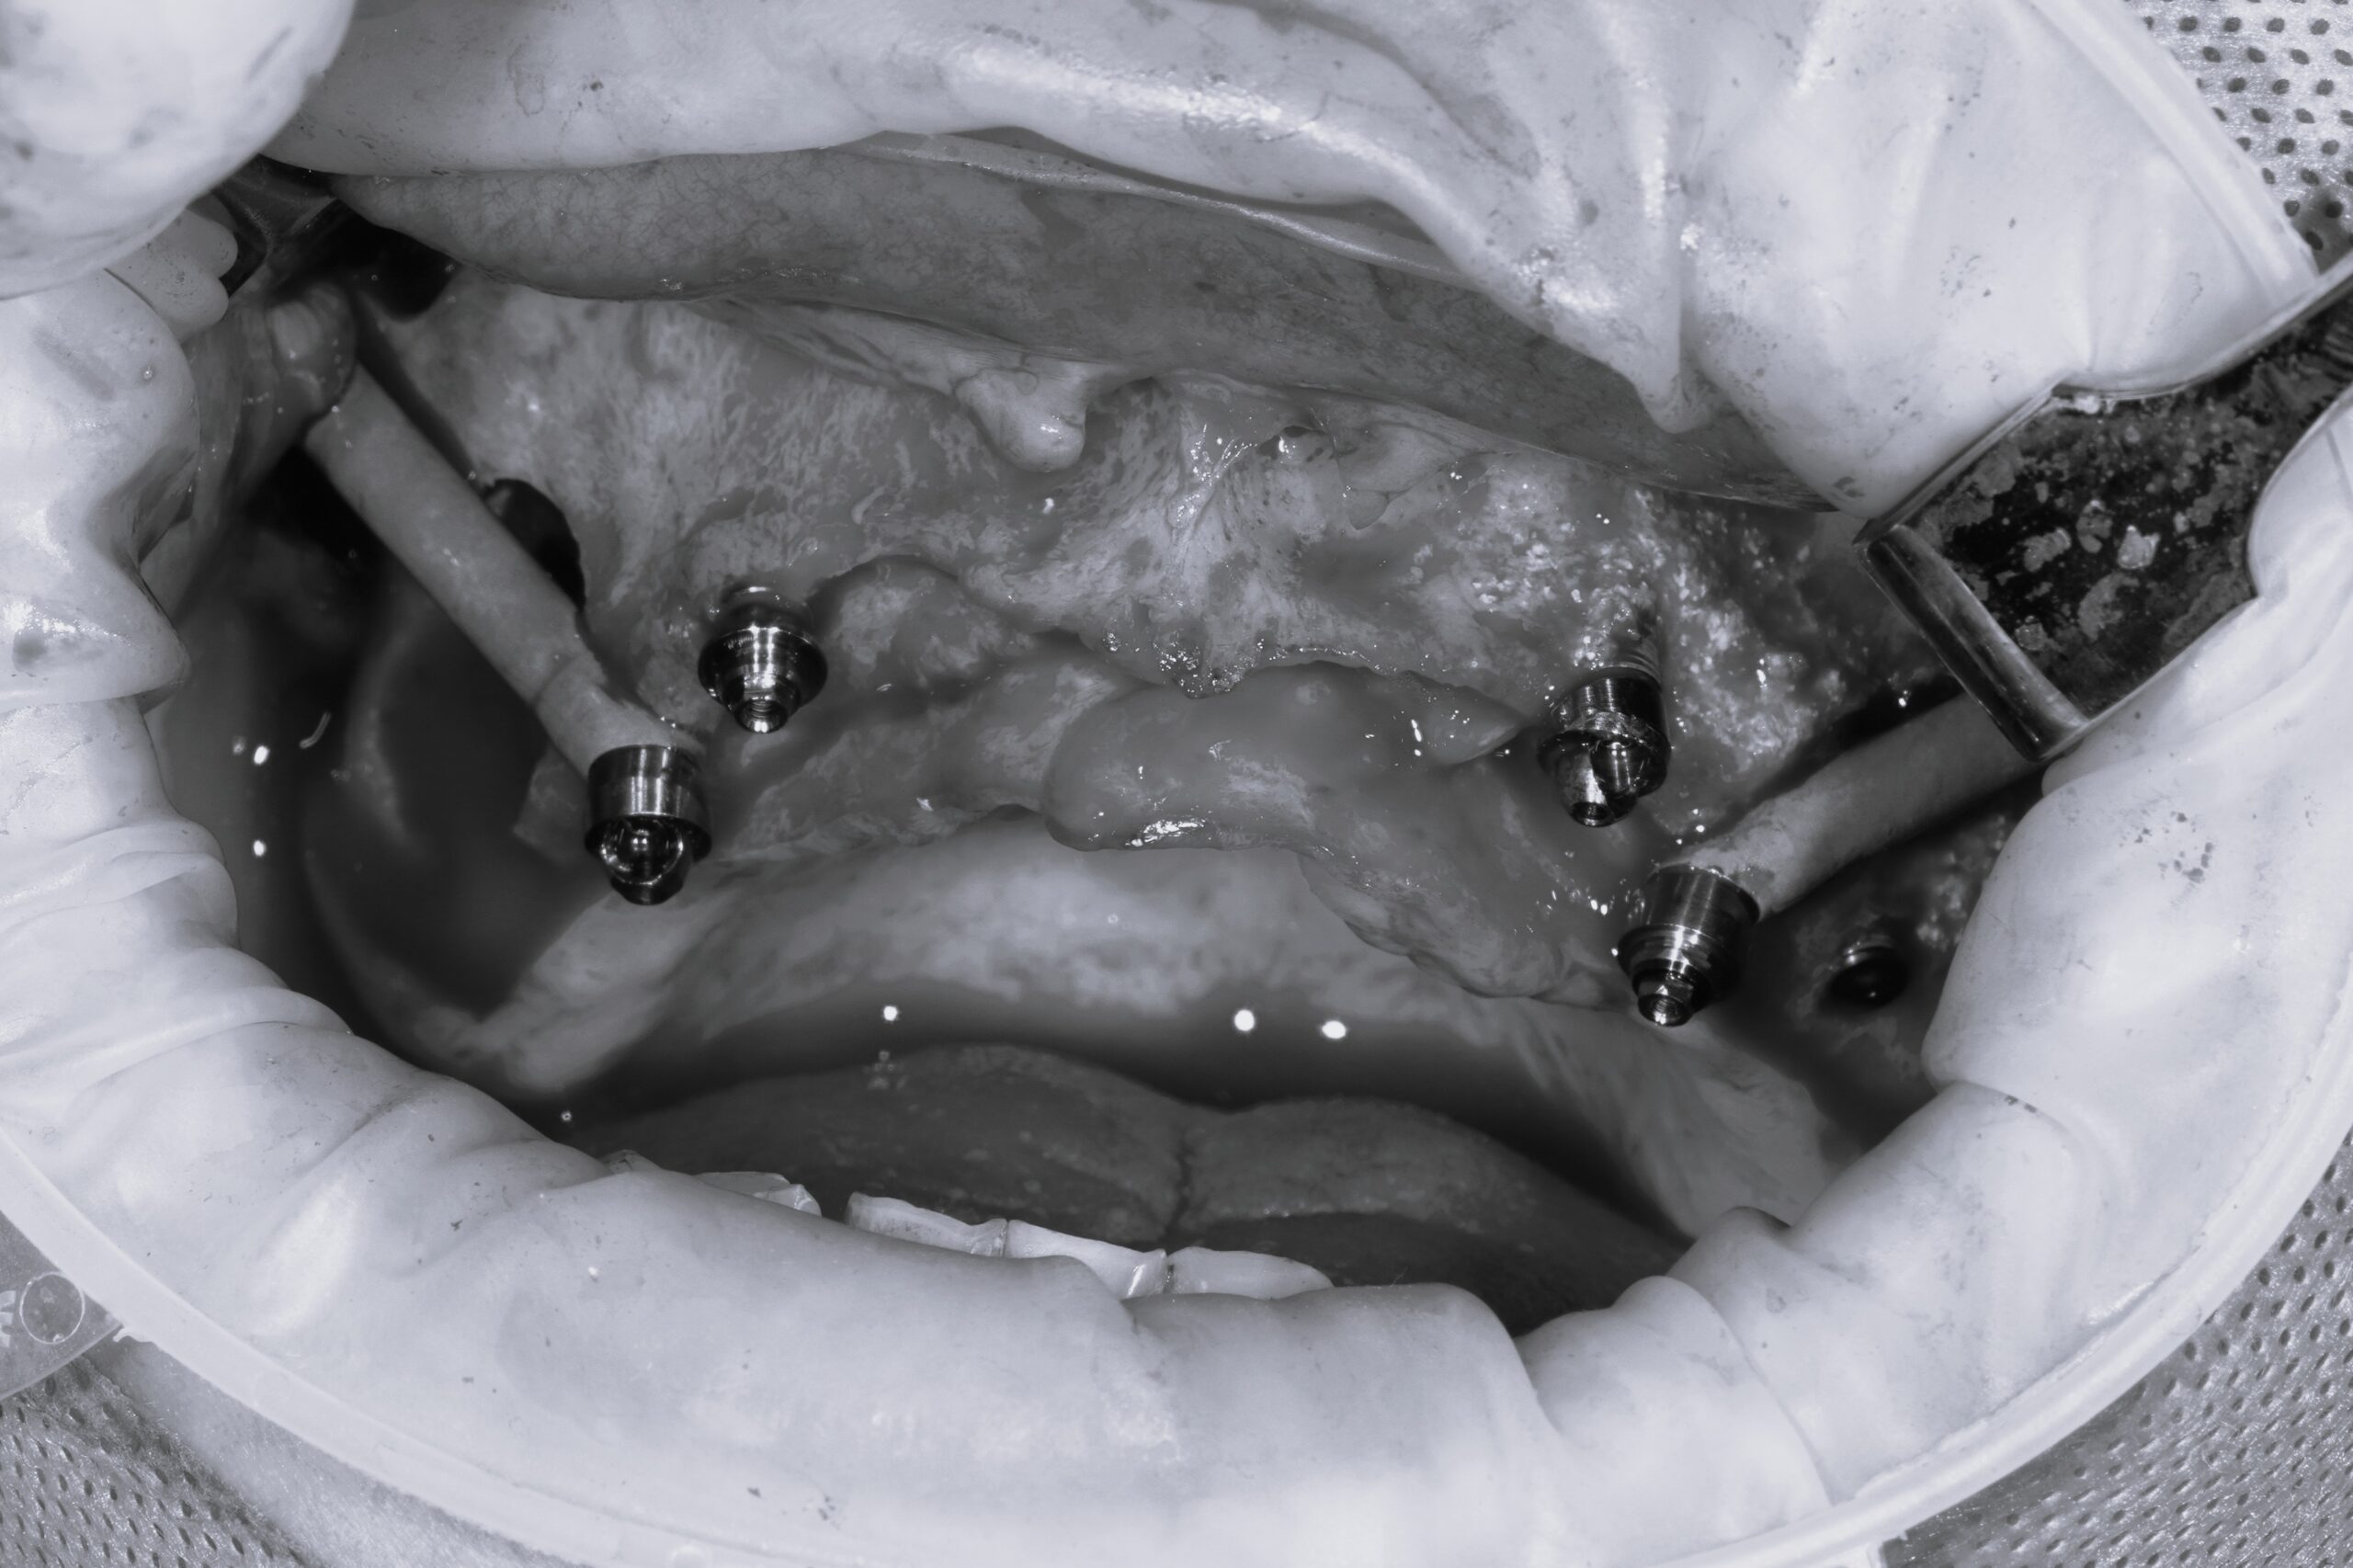

顴骨植牙是一種專為嚴重上顎骨流失的患者設計的高級植牙技術,與傳統植牙不同,植體固定在顴骨上,而不是齒槽骨,因此即使患者的齒槽骨萎縮,也能成功植牙。

✅ 術前規劃:透過3D電腦斷層掃描(CBCT)精確評估顴骨結構

✅ 植體品質:使用國際認證的植體品牌,如Nobel Biocare的Zygoma植體,確保穩定性